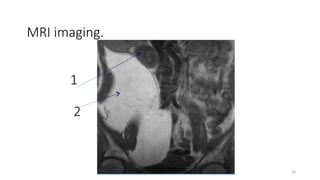

MRI imaging.

1

2